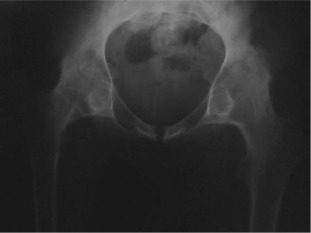

There were 61 patients (50 male, 11 female) with 105 affected hips (72% bilateral, 28% unilateral). The average patient age at surgery was 41.3 ± 10.2 years old. The age of patients at THA was as follows: <30 years for 14 patients (23 hips), 31–50 years for 41 patients (73 hips) and >50 years for 6 patients (9 hips) (Graph 1 ). The younger age at diagnosis (<30 years old) of AS was correlated with younger age at THA (p < 0.05). Bone ankylosis was detected in 37 (35%) and acetabular protrusion was noticed in 18 (17%) hips in pre-operative radiographs (Fig. 1 , Fig. 2 , Fig. 3 ; Fig. 4 ) (Table 1 ). The mean pre-operative flexion contracture was 20.3°±21.8°. In patients without ankylosis, the mean total hip range of motion (ROM) was 67.8°±25.7°.

Fig. 4. Six years after right side, five years after left side THA. |